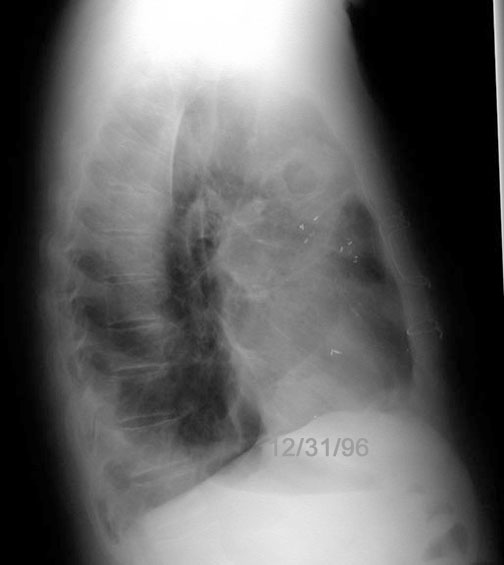

Case 37

Lateral

Labeled Image

How do you distinguish LL lung abscess from hiatal hernia?